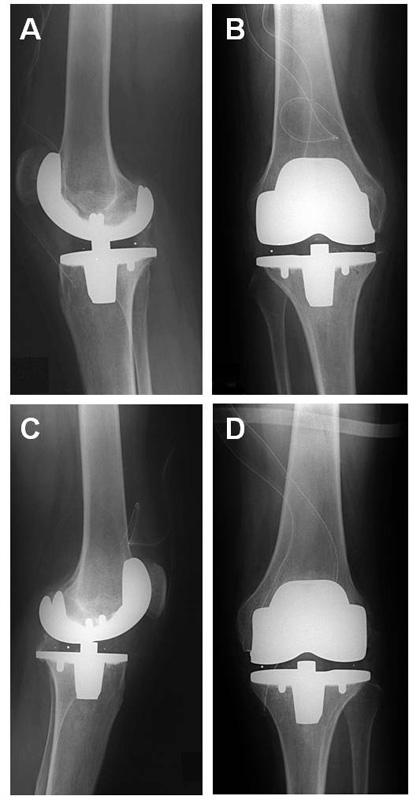

Figure 2

X-rays of both knees after surgical implantation of prostheses. (a) Right knee lateral view (b) Right knee anterior-posterior view (c) Left knee lateral view (d) Left knee anterior-posterior view.

The patient was hospitalised four days before the operation. Responding inhibitor activity level was high, measured as 2 Bethesda units (standard value is supposed to be negative). A Mahourkar catheter was inserted for delivery of extracorporeal immunoabsorption treatment and rFVIIa (120 μg/kg body weight) was administered. Additionally, APCC was given on day 1 and day 3 before the operation with each 6000 IU. On the basis of this treatment there was no elevated inhibitor titre on the day of the operation. Thus, 100 IU/kg body weight of factor VIII ([FVIII], Haemate HS Aventis ZLB Behring®, King of Prussia, PA, USA) was given for the operation. After reaching a normal aPTT (activated partial thromboplastin time) bilateral simultaneous total knee arthroplasty was performed under general anaesthesia, starting on the right side. The right knee was technically more demanding and clinically more symptomatic. Tourniquet time for the right knee was 103 minutes and for the left knee 115 minutes. The surgery was performed using a midline incision with medial parapatellar arthrotomy. To mobilise the knees extensive adhesiolysis of the dorsal capsule and the collateral ligaments had to be performed. The course of surgery was uneventful with no major bleeding occurring. Estimated blood loss amounted to 1000 mL for each procedure. Both components (femoral and tibial) were cemented with an ultra congruent tibial polyethylene plateau sacrificing the posterior cruciate ligaments (Innex® Sulzer AG, Baar, Switzerland). After implantation the passive range of motion was 80-5-0° (flexion/extension) for both knees, with a soft endpoint in extension. Before closing the wound the tourniquet was opened and meticulous inspection of the surgical area was performed to detect minor bleeding sources (fig. 2).